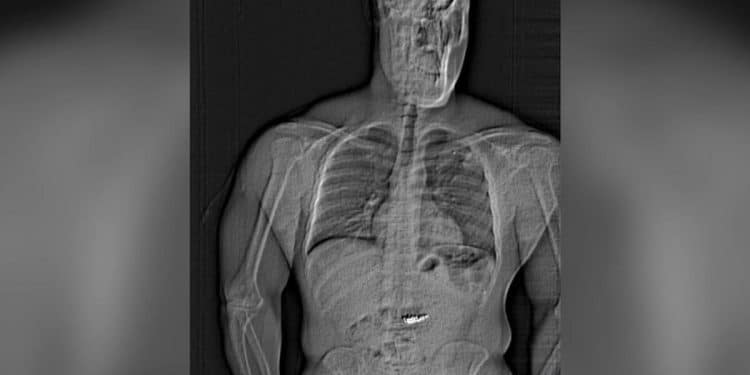

A man posing as an NBA player’s representative in Orlando, Florida, stole and swallowed more than $700,000 worth of Tiffany jewelry, police say. The suspect is now facing charges of grand theft and robbery.